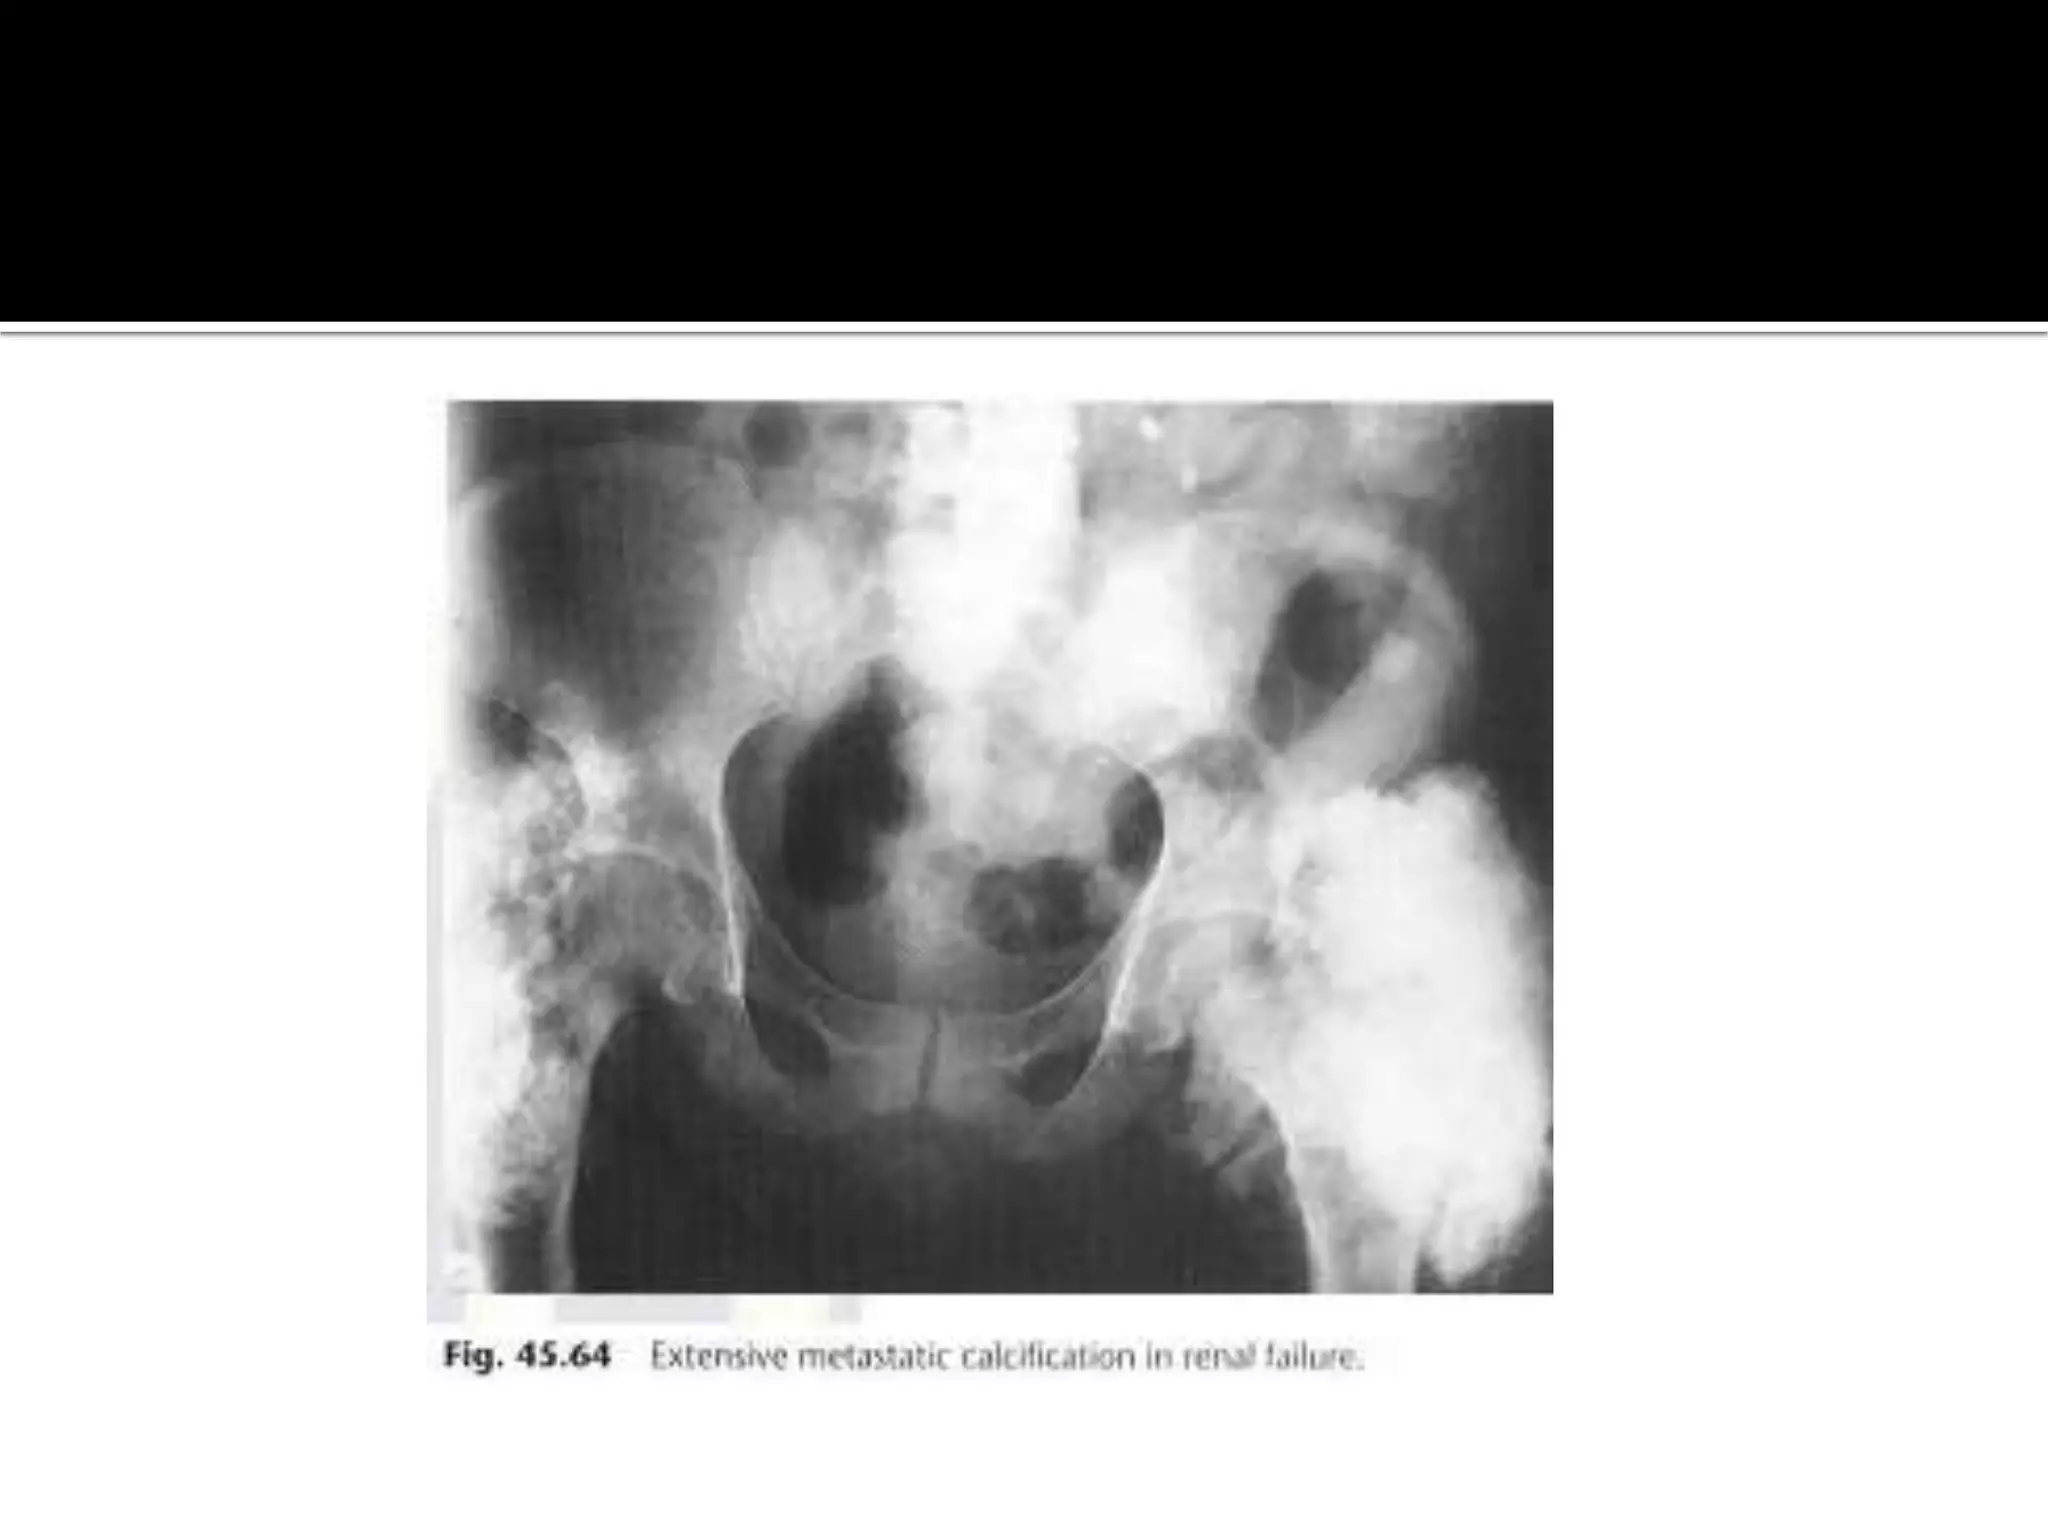

 Metabolic and metastatic calcification is the result

of abnormal calcium and or phosphate metabolism,

in particular any cause of hypercalcemia. commonly

occurs in secondary hyperparathyroidism

Periarticular calcinosis

 develops as well as metastatic calcification in the

soft tissues.This may be so extensive that layering

of the calcium is seen.With treatment of

hypercalcemia the soft tissue calcification may

resolves.

 Hydatid cystsin the soft tissues is rare Calcification in Metabolic disorders.  Metabolic and metastatic calcification is the result of abnormal calcium and or phosphate metabolism, in particular any cause of hypercalcemia. commonly occurs in secondary hyperparathyroidism

• 23.

Periarticular calcinosis  developsas well as metastatic calcification in the soft tissues.This may be so extensive that layering of the calcium is seen.With treatment of hypercalcemia the soft tissue calcification may resolves.  Periarticular and interstitial calcinosis may be seen with hypoparathyroidism.